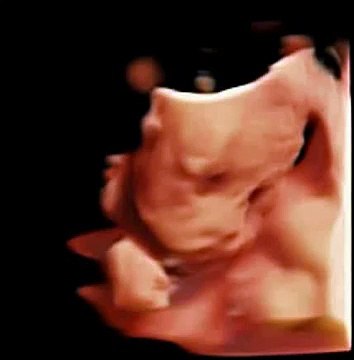

This viral video shows how active unborn babies can be in the womb and it's a lot of fun for expectaThis video of an unborn baby has had more than six million views - because the little one looks like it's DANCING in the womb. The amazing footage is from a 4D ultrasound scan - and it really looks like the foetus is bopping away inside its expectant mum , although no more is know about her identity. Originally shared on medical social network Meddy Bear's Facebook page on December 19, it came from the site in Ukraine, where doctors, nurses and medical staff can post unusual, entertaining or interesting news about their roles. While many of us are familiar with 3D ultrasound images which show still images of unborn babies , 4D scans can show moving 3D images. Read more: Heartwarming picture shows 'angel' watching over unborn baby in ultrasound scan The foetus is seen in a variety of positions, moving its limbs and even kicking out against the womb, before giving what looks like a big yawn.nt parents to watchThe Facebook response to the post has been colossal, with many remarking on how much the 4D scan can show expectant parents. Connie Girlando wrote: Wow, 4D ultrasound, that's beyond amazing... to think that is all they know. Facebooker Kirsty Hartley added: Wow! Freaks me out a little bit to see how much the baby moves (not had one yet) but also amazing.